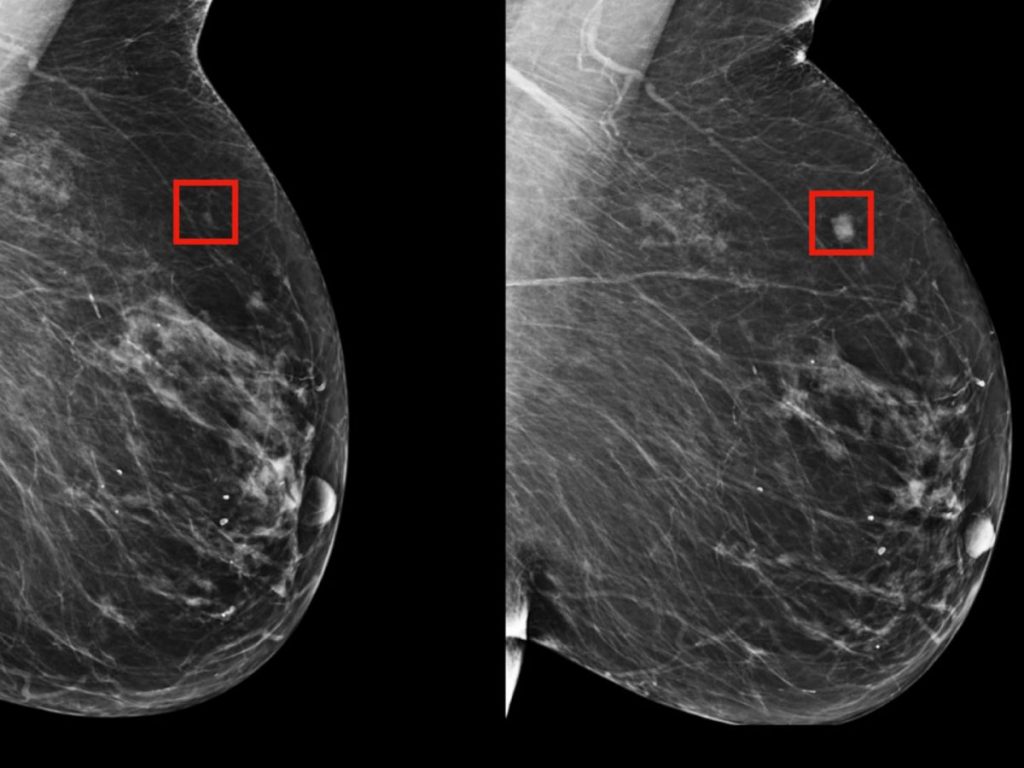

Le modèle développé au Massachusetts Institute of Technology ne cherche pas une tumeur.

Il cherche une probabilité.

Une trajectoire possible.

Un futur à peine perceptible, qui ne crie pas — il murmure.